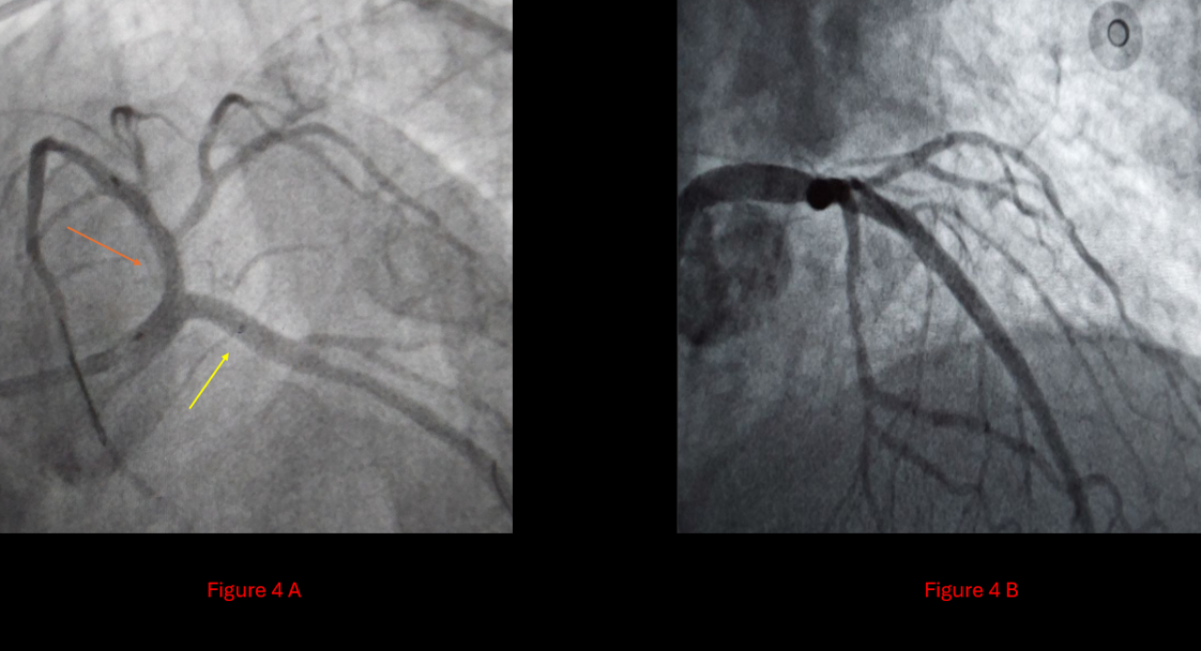

In the absence of other viable options, intravascular lithotripsy (IVL) was employed—a challenging and resource-intensive choice, particularly in a low-income setting such as Jordan. Shockwave Lithotripsy was applied with 70 pulses to the LAD and 10 pulses to the Cx. This allowed successful modification of the calcified lesions, creating a safe environment for definitive bifurcation intervention. A Double-Kiss Crush (DK-Crush) stenting technique was then performed for the LM-LAD-Cx bifurcation, employing a 1:1:1 Medina classification strategy (Figure 3). A new drug-eluting stent was deployed in the LAD, with final angiography showing fully patent three-vessel flow (Figure 4).

Figure 4: Showing the outcome after the DKC technique.

4A: Orange arrow: new stent in the LAD, yellow arrow: stent in the Cx.

4B: Patent LM, LAD, and cx